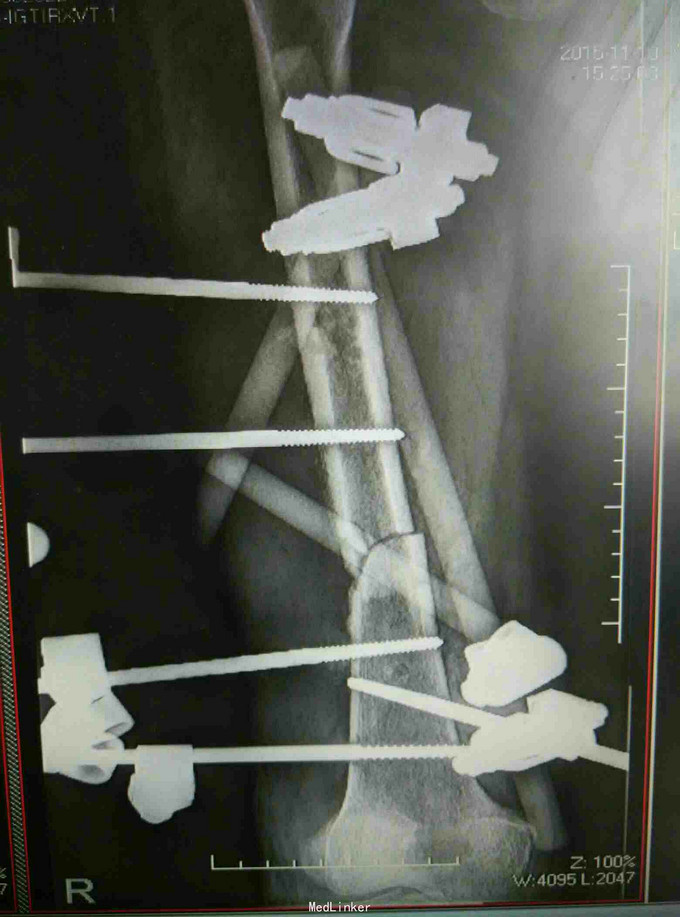

车祸致昏迷伴全身多处出血12小时 患者因车祸被撞后昏迷,伴有全身多处损伤出血,右小腿可见骨外露,患者于当地医院行补液输血,患肢清创包扎石膏外固定后送入我院。

查体:昏迷,平车推入病房,因昏迷骨盆挤压分离实验无法配合,患者双上肢被动活动可,右小腿绷带包扎,解开纱布见胫骨骨外露,可闻及异味,对侧下肢被动活动可。 辅查:摄片提示右股骨干骨折,右胫腓骨骨折

诊断:右股骨干骨折 右胫骨开放性骨折 右腓骨骨折 治疗:开放性骨折清创,骨折外固定架固定

随访:定期换药,注意预防钉道感染,定期复查视情况拆除外固定。 讨论:患者昏迷入院,颅脑也有损伤,下肢开放骨折入院时已出现感染迹象,行彻底清创,行外固定支架固定。对软组织情况不佳的患者切忌盲目内固定,特别是在胫骨跟骨这些紧贴皮肤的部位。